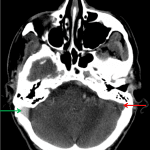

- Mass effect on the left internal jugular vein with occlusive thrombus in the left internal jugular vein extending cranially from the level of C1-C2 into the imaged portions of the left sigmoid and transverse sinsuses

Associated compression of the left internal jugular vein with occlusive thrombus extending cranially from the level of C1-C2 into the visualized portions of the left sigmoid and transverse sinuses. Recommend brain MRI with and without contrast for further assessment.